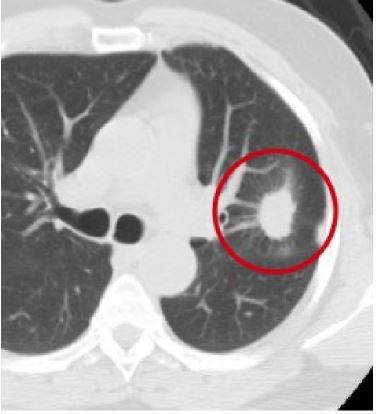

12

Q

-imaging modality -orientation -window -body part -iv contrast -abnormality

A

-CT -axial -lung -chest -yes -left lung carcinoma

How well did you know this?

13

what do hazy edges of a tumor on a CT mean?

-cancer is invading surrounding tissue